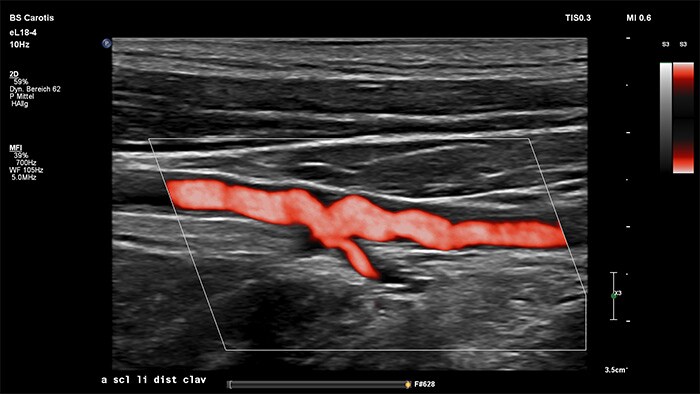

MicroFlow Imaging de Philips se ha diseñado para identificar con una extraordinaria sensibilidad las zonas anatómicas que presentan un flujo sanguíneo lento y débil en los tejidos y, además, mejora la resolución del flujo en las exploraciones vasculares. Gracias a su alta resolución y cantidad mínima de artefactos, los profesionales sanitarios pueden visualizar y caracterizar alteraciones sutiles en el flujo alrededor de la placa estenótica para así elaborar diagnósticos fiables.